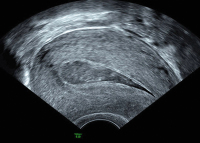

Ultraschall-Serometra

Abbildung 1: Serometra bei Asherman-Syndrom nach manueller Plazentalösung und dreimaliger Abrasio nach der letzten Entbindung. Dank der Flüssigkeit kann man erkennen, dass praktisch keine Endometrium-Schleimhaut aufgebaut ist.